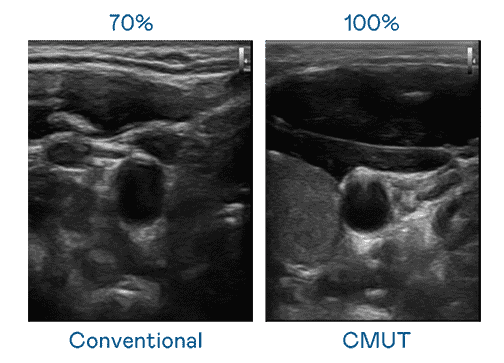

CMUT 技术是一种用电容式微机电元件来产生超音波讯号的技术。。。与传统 PZT 压电式技术相比,,,,CMUT 频宽增加 30%,,,,更宽频的超音波讯号让影像解析度大幅提升,,是实现高影像品质医疗超音波扫描、、、促进精准医疗发展的关键技术。。。。

大频宽带来超清晰影像

超音波影像的解析度高低,,首先取决于探头能发出的讯号频宽。。。云顶国际8588yd CMUT 可提供高清晰的超音波讯号,,,提供高频宽、、高灵敏度、、、影像纹理细节更高的超音波影像,,,,协助医护人员缩短影像判读时间及利用精准的医疗影像进行诊断。。。